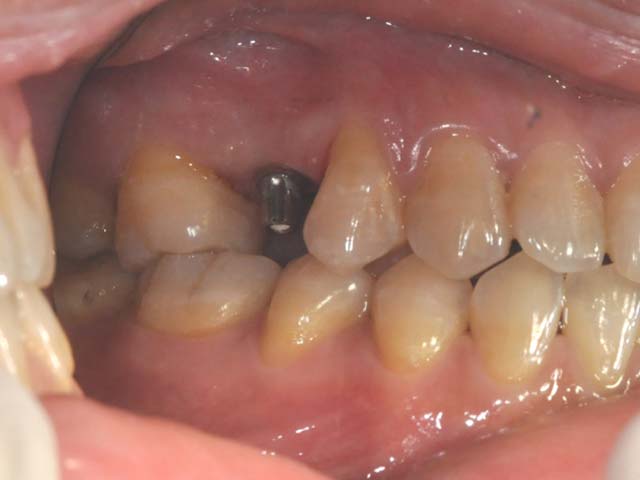

齒槽骨保存術+植牙 首頁 案例分享 人工植牙 齒槽骨保存術+植牙 STEP1拔除掉無法使用的斷裂牙根 STEP2齒槽骨保存術—使用骨粉填補拔牙傷口 術前 V.S 術後 植牙第一階段—植入牙根 植牙第二階段—製作正式假牙